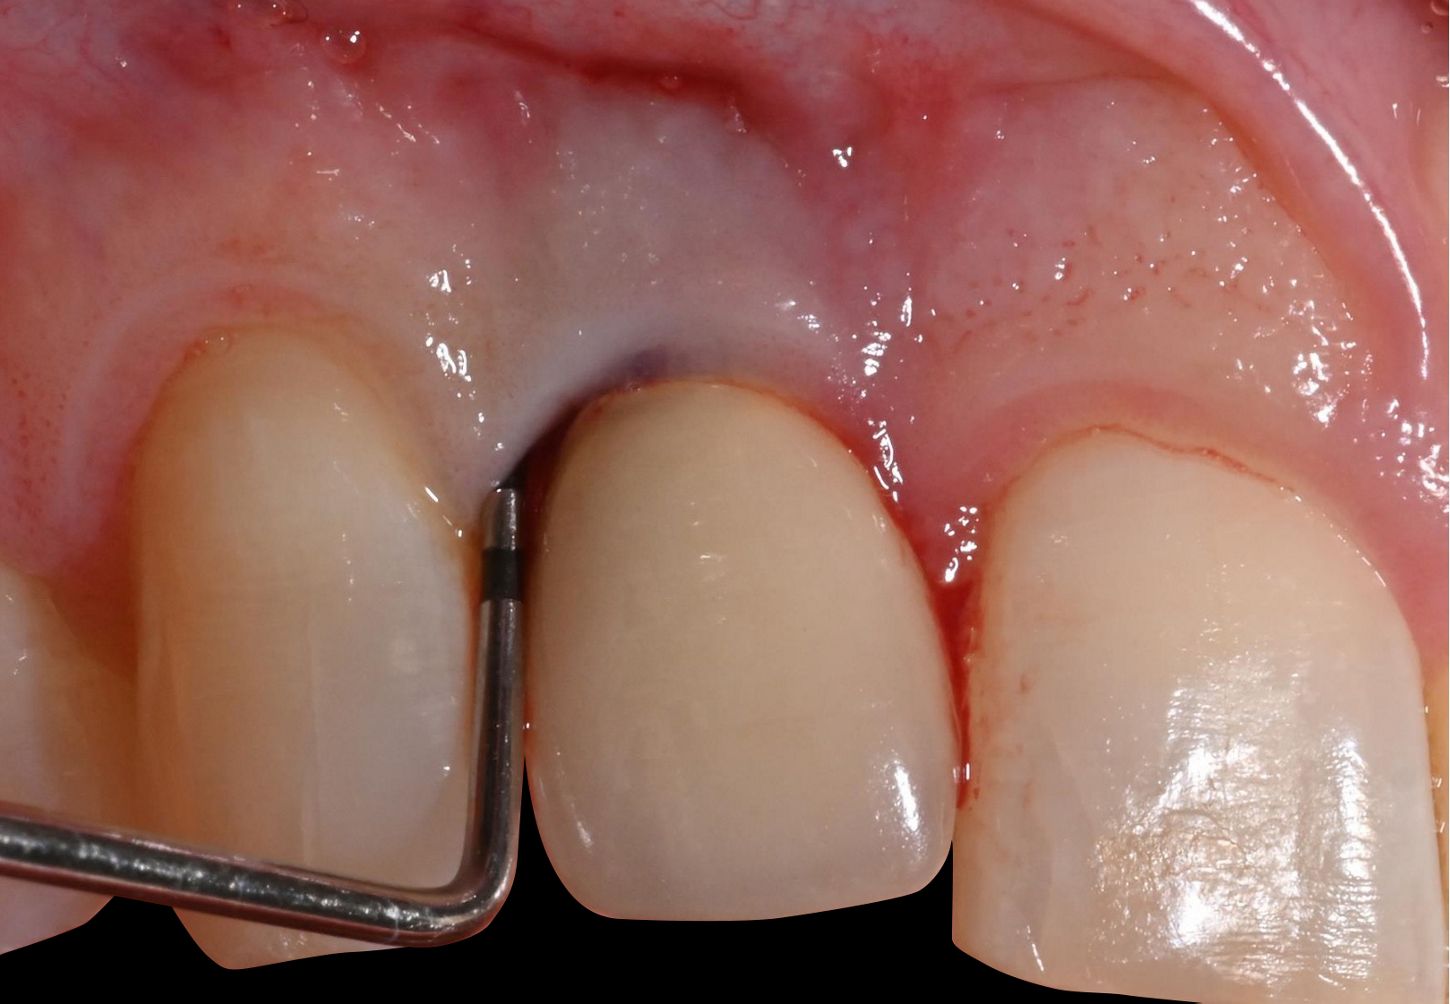

Male, 38 years, implant (Frialit) in region 12 (FDA) seated approximately 20 years ago. The tooth was lost after a trauma. The patient is now referred for treatment of peri-implantitis. The patient's esthetic concern is relatively high, but he has a low smile line. Fully healthy and a non-smoker. No signs of periodontal disease, generally good plaque control but sporadic signs of marginal and papillary gingivitis in the posterior segments. Radiographic and clinical examination demonstrates advanced peri-implant bone loss at implant in region 12 (FDA), with pronounced signs of inflammation. Diagnosis: Localized advanced peri-implantitis.

After careful oral hygiene instruction and localized non-surgical treatment with Labrida BioClean™ the patient was scheduled for surgery. Baseline pocket probing depths were 8-9 mm with positive BoP scores. The rationale for the surgical strategy used on this implant with peri-implantitis was to reconstruct the peri-implant osseous defect with bone using a slowly resorbable xenogenic graft, while EMD was to be used to accomplish optimal soft tissue healing in the esthetic zone. The combination of mechanical and chemical decontamination of the implant surface with Labrida BioClean™ and Straumann PrefGel® was to be used to prepare the implant surface for the graft material.